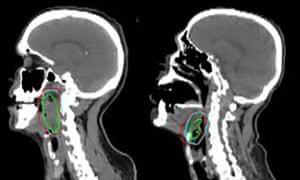

Targeting head and neck tumours